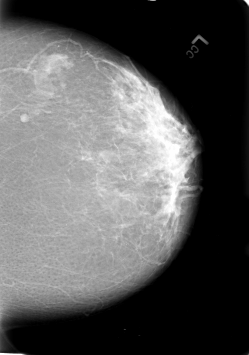

B_3020_1.RIGHT_CC

B_3020_1.LEFT_CC

LEFT_CC LINES 5672 PIXELS_PER_LINE 3976 BITS_PER_PIXEL 12 RESOLUTION 50 NON_OVERLAY

RIGHT_CC LINES 5624 PIXELS_PER_LINE 4008 BITS_PER_PIXEL 12 RESOLUTION 50 OVERLAY